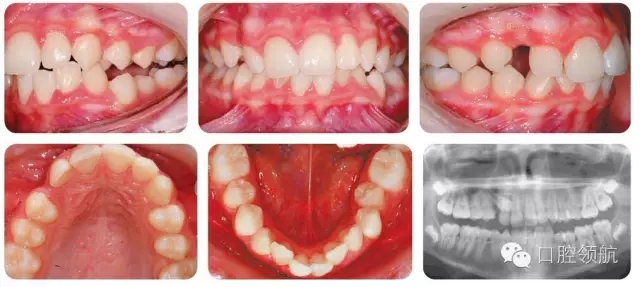

影像學(xué)檢查結(jié)果(圖3.8)

● UR3近中傾斜阻生。

● UR3牙尖覆蓋于側(cè)切牙唇側(cè),有利于牽引助萌。

● 沒有相關(guān)病理因素。

● 4顆第三磨牙均存在。

13歲男性患者,安氏I類咬合關(guān)系,骨性I類均面型,UR3異位,上下牙列擁擠伴中線不齊(圖3.8)。